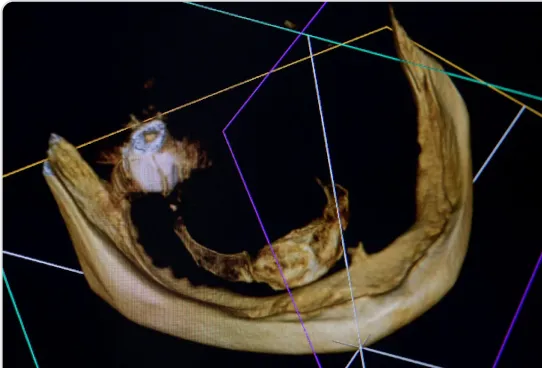

TRÓJWYMIAROWA REKONSTRUKCJA WYROSTKA ZĘBODOŁOWEGO PRZY UŻYCIU INDYWIDUALNIE DRUKOWANYCH SIATEK TYTANOWYCH YXOSS ReOss

To kolejna metoda umożliwiająca precyzyjną odbudowę zadanego kształtu tkanki kostnej przy użyciu standardowych materiałów kościotwórczych, kości własnej lub PRF oraz zewnętrznego rusztowania w postaci siatki z biozgodnego stopu tytanu. Siatka jest indywidualnie projektowana w technologii CAD CAM i następnie drukowana dla konkretnego przypadku.

Dotychczas stosowane stabilizatory zewnętrzne w formie siatek tytanowych używane do regeneracji kostnej lub w zabiegach odtwórczych w chirurgii szczękowo-twarzowej uwzględniały materiały ręcznie doginane i formowane podczas zabiegu operacyjnego. Zastosowanie technologii CAD CAM dla potrzeb druku materiałów przeznaczonych do indywidualnej rekonstrukcji kostnej znacznie poprawiło precyzję i jakość uzyskiwanych efektów. Wdrożenie biozgodnych stopów tytanu do druku siatek zdecydowanie ograniczyło odsetek powikłań zapalnych.

Precyzja projektu druku siatki bazuje na dokładności odwzorowania kształtu kości w stożkowej tomografii komputerowej CBCT, co zapewnia ich dobre przyleganie do podłoża kostnego oraz ogranicza powstawanie powikłań w postaci obnażania się siatek. Precyzja projektu oraz materiał, z którego wykonana jest siatka (biozgodny stop tytanu), powodują, że obnażenie się siatki nie zaburza procesu gojenia i regeneracji kostnej.

Wymaga jedynie większej ilości kontroli pozabiegowych oraz wzmaga czujność higieniczną zarówno ze strony lekarza, jak i pacjenta. Ten rodzaj odbudowy kostnej stosowany jest w sytuacjach złożonych, trójwymiarowych 3D ubytków kości, przy których standardowe metody odbudowy są niewystarczające. Ilość kości, którą możemy uzyskać, stosując tę metodę, to nawet kilka centymetrów sześciennych.

Metoda rekonstrukcji kostnej w oparciu o indywidualnie drukowane siatki z tytanu dla implantacji wszczepów śródkostnych stosowana jest najczęściej jako dwuetapowa. W pierwszym etapie odbudowywana jest kość, natomiast implanty wszczepiane są po okresie 4–6 miesięcy. Na wgojenie implantów oczekujemy od 4 do 6 miesięcy w zależności od miejsca ich lokalizacji. Siatka tytanowa po spełnieniu swojej funkcji rusztowania dla odbudowującej się kości jest następnie usuwana w dniu wszczepienia implantu. Jeżeli kość spełnia odpowiednie warunki, istnieje możliwość zastosowania modyfikacji siatki tytanowej, która umożliwia jednoczesne wprowadzenie implantów wraz z odbudową kostną.

Wariant ten skraca czas od pierwszego zabiegu do wykonania gotowych koron protetycznych na wprowadzonych implantach. Opisane schematy procedur regeneracyjnych wykazują znaczną innowacyjność, jeśli chodzi o wykorzystanie technologii cyfrowej w medycynie odtwórczej. Natomiast w codziennej praktyce chirurgicznej poprawiają precyzję, tempo oraz przewidywalność w świadczeniu usług polegających na odbudowie zniszczonych lub zdeformowanych ludzkich tkanek.